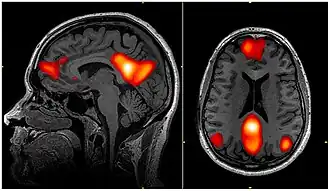

![]() Imagem de fMRI mostrando regiões da rede de modo padrão

Na neurociência, a rede de modo padrão (DMN, do inglês Default Mode Network, ou RMP), também rede padrão, ou rede cerebral padrão, é uma rede cerebral de larga escala de regiões do cérebro em interação, conhecidas por terem atividade altamente correlacionada entre si e distinta de outras redes no cérebro.[3]